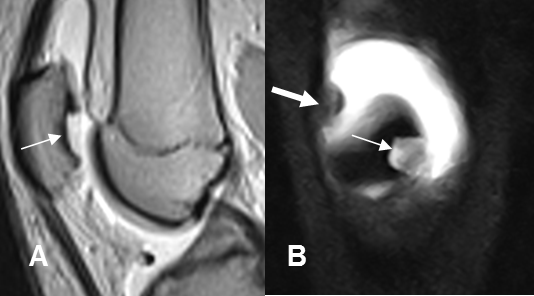

Fig 203. Lesión osteocondral inestable.

A: Rx AP. Area densa sobre el cóndilo femoral lateral.

B: RM sagital en T1. La imagen corresponde a lesión osteocondral.

C: RM coronal en STIR y D: RM coronal en T2. Lesión osteocondral con bordes hiperintensos, lo que indica inestabilidad.